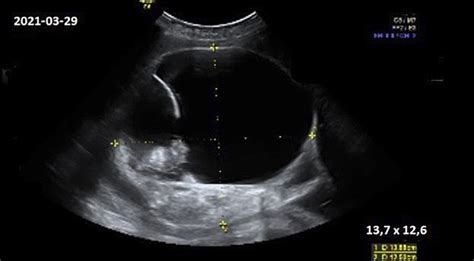

Echoskopija, dar vadinama ultragarsiniu tyrimu, yra pažangus diagnostikos metodas, leidžiantis stebėti paciento vidaus organų judėjimą, kraujotaką ir kitus organizmo sistemų pokyčius realiu laiku. Ji veikia naudojant aukšto dažnio garso bangas, vadinamas ultragarsu, kurių žmogaus ausis negirdi. Šios bangos, siunčiamos specialaus daviklio (zondo), atsimuša nuo skirtingų audinių ir organų, o grįžtantis „aidų“ signalas yra apdorojamas ir paverčiamas vaizdu ekrane. Šis procesas yra visiškai nekenksmingas, nes nenaudojama jonizuojanti spinduliuotė, skirtingai nei radiologiniuose tyrimuose, tokiuose kaip rentgenas ar kompiuterinė tomografija. Dėl šios priežasties echoskopija yra saugi ir gali būti atliekama tiek suaugusiems, tiek vaikams, net ir nėščioms moterims.

Įrenginys, vadinamas echoskopu, naudoja ultragarsinį daviklį, pagamintą iš bario titanato ar kitų pjezokristalų. Veikiami elektros srovės, šie kristalai spinduliuoja ultragarso bangas. Per sekundę įrenginys sukuria 300-1000 impulsų, kurių energija nukreipiama į audinį. Susidūrusios su audiniu ar skysčiu, bangos atsispindi ir grįžta į daviklį, kur jos paverčiamos elektros impulsais ir registruojamos oscilografu. Tai leidžia sugeneruoti dvimatį (2D) vaizdą, kuriame matoma organo ar audinio padėtis, struktūra ir dydis. Dėl didelio impulsų skaičiaus galima įvertinti judančias struktūras, o naudojant nedidelius dažnio pokyčius (Doplerio efektą), galima įvertinti kraujo tėkmės greitį ir spręsti apie kraujagyslių būklę.

Be to, echoskopija plačiai naudojama akušerijoje, kurios metu gydytojas gali stebėti vaisiaus augimą, diagnozuoti apsigimimus, nustatyti vaisiaus lytį ir padėtį.